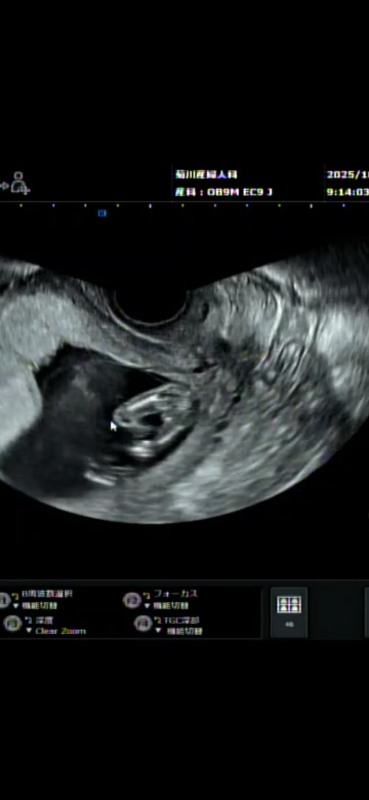

性別については、妊娠16~17週くらいから判定できる場合もありますが、一般的には、妊娠18~20週に分かることが多いようです。また、21週を過ぎるとより判別がつきやすくなります。早い人だと妊娠12~14週でぼんやりわかることもあります。お写真を拝見しましたが、このお写真からでは、ハッキリと性別は分かりません。せっかくご相談いただきましたのに、お役に立てず申し訳ありません。ママさんとしては、なかなか性別がハッキリしないと、モヤモヤしてしまいますし、お名前を決めたり、赤ちゃんグッズの準備もありますよね。赤ちゃんの位置や向きによって、なかなか見せてくれない場合もありますが、健診時に聞いていただくのは問題ないので、またご確認なさってくださいね。